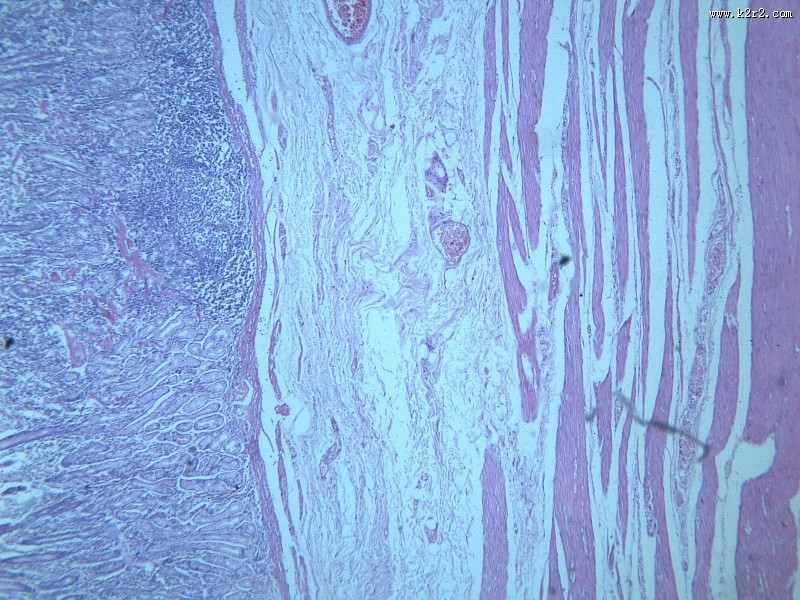

慢性萎缩性胃炎大全 - 第4张

慢性萎缩性胃炎大全

chronic atrophic gastritis

慢性萎缩性胃炎

消化道疾病